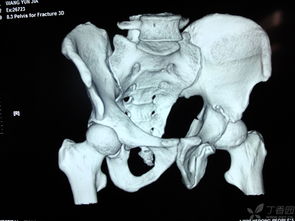

髖臼骨折,恥骨骨折,經(jīng)檢查無需住院,2回答者:lianghuanjie